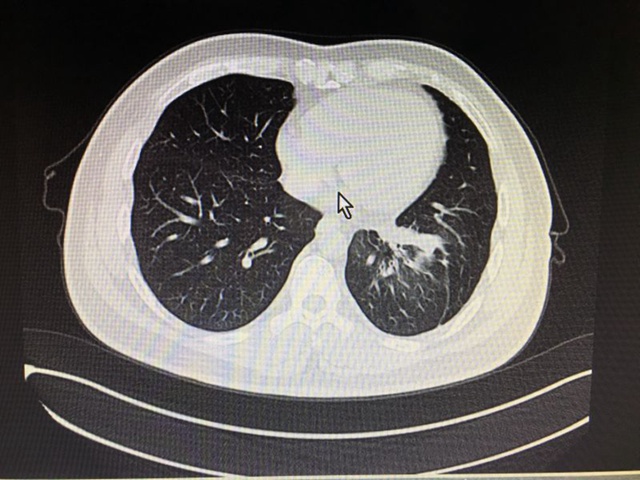

服用靶向药后(2016.2.6)CT影像: